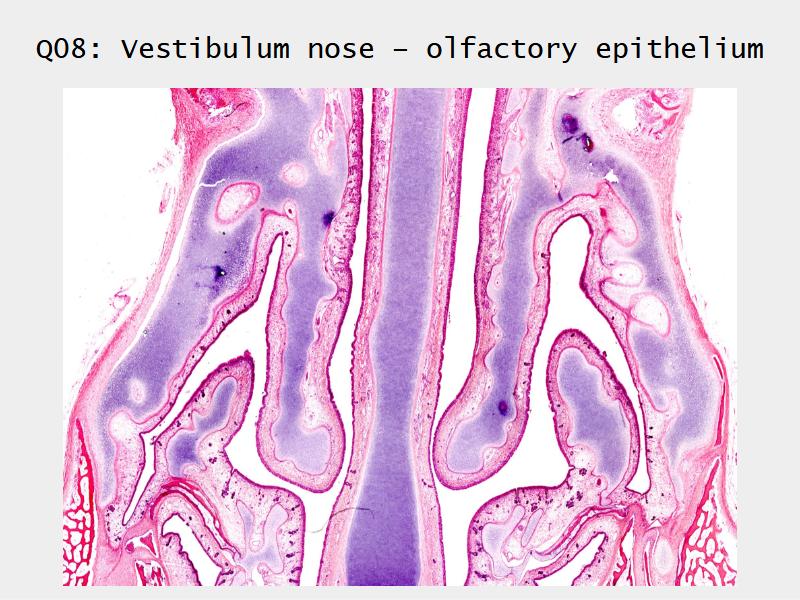

Slides: Respiratory System

- Slide 71: Nostril

- Slide 108: Olfactory epithelium

Olfactory epithelium

Function of the nasal cavity?

Function of the nasal cavity?

- Warm

- Moisture

- Filter

- Smell